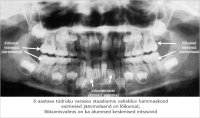

Jäävhammaste lõikumine

1

Poster